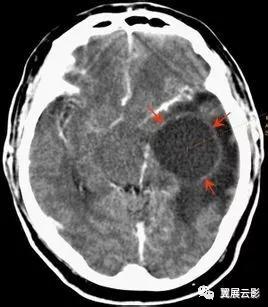

病例1:脑出血(急性期)

脑出血重点应在诊断报告中写明出血的部位,大小或出血量,出血在T1WI和T2WI上信号特点,水肿情况及占位效应,鉴别诊断时应注意排除肿瘤卒中及脑血管畸形合并出血。